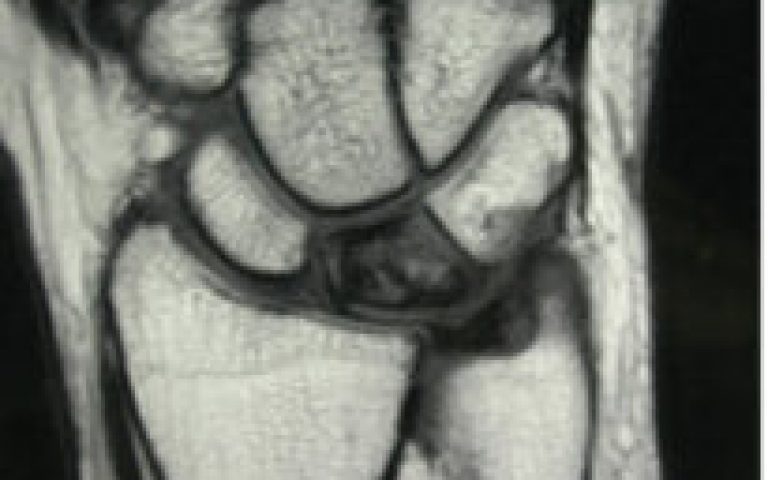

Polyarthrite rhumatoïde

Pathologies de la Main et du poignet Maladie de Kienbock

Maladie de Kienbock